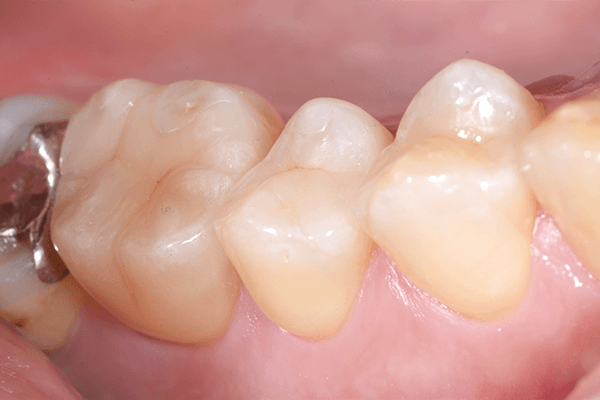

1.術前の口腔内写真

右上奥歯(上顎右側第一大臼歯)に冷たいものが強くしみる症状があります。